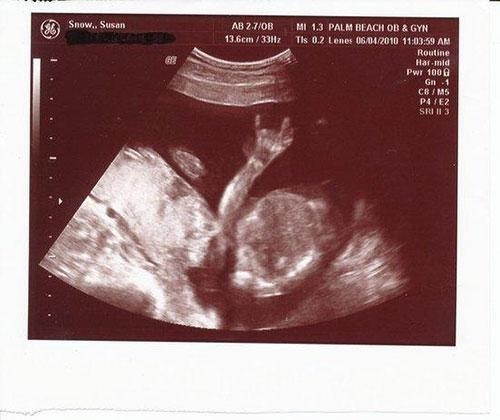

BEBEĞİN CİNSİYETİNİ ÖĞRENECEKLERDİ AMA... ULTRASONU GÖRÜNCE ŞOKE OLDULAR !

Bebeklerinin Cinsiyetlerini Öğrenmek İstediler Fakat Hayatlarının Şokunu Yaşadılar!